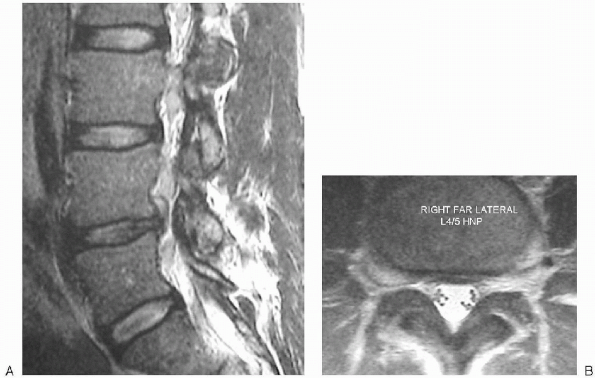

![]() |

|

FIGURE 17-3. Magnetic resonance imaging views of a large L4-5 disc herniation, sagittal (A) and axial (B).

notable for affecting the upper root. For example, a far-lateral L4-5

herniation affects the upper L4 root after it exits from under the L4

pedicle, rather than affecting the more medial L5 root (Figs. 17-3, 17-4 and 17-5).